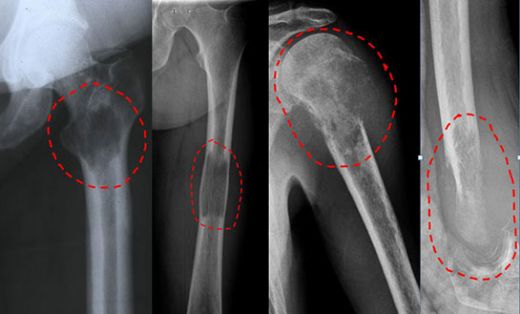

Akciğer kanserinin metastaz yapması maalesef genellikle geç fark ediliyor. Metastazın belirtileri, kanserin yayıldığı organlara bağlı olarak değişebilir. Örneğin, karaciğere yayıldığında sarılık, karın ağrısı ve kilo kaybı gibi belirtiler ortaya çıkabilir. Kemiklere metastaz yaptığında ise kemik ağrıları ve kırılma riskinde artış görülür.